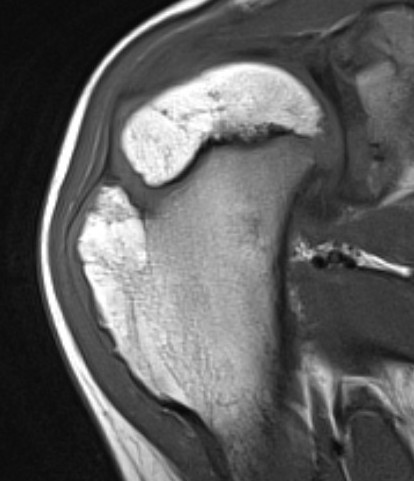

MRI

Cartilage cap iso-intense with hyaline cartilage

Suspicious features

- growth after maturity

- increased thickness of cartilage cap on CT / MRI - > 2 cm

- increasing pain

- increased calcification / bony erosion / lytic areas on xray

- septal enhancement after MRI with gadolinium

- MRI / CT of 64 benign osteochondromas and 34 secondary chondrosarcomas

- cartilage cap 2 cm or more 100% sensitive and 98% specific for secondary chondrosarcoma

Proximal humerus

Bae et al J Pediatr Orthop 2014

- 31 patients with proximal humerus osteochondromas

- anterior / lateral / posterolateral debulked 92%

- posteromedial debulked 68%

- recurrence 2/31 (6.5%)